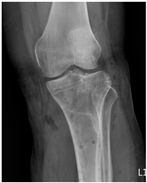

The case report presents three patients with different sites of fractures (Table 1), involving two female and one male patients, who underwent removal of a titanium-based plate in a regional hospital in Taiwan. Before the removal of the plates, all patients had previously undergone Open Reduction and Internal Fixation (ORIF) of fractures using titanium-based plates, specifically “Ti-6Al-4V” (90% titanium, 6% aluminum, 4% vanadium, 0.25% iron, and 0.2% oxygen). The manifestations and the radiographs of the operative site are summarized in Table 2.

Table 2.

Clinical appearance and radiographic images before and after titanium-alloy implant removal.